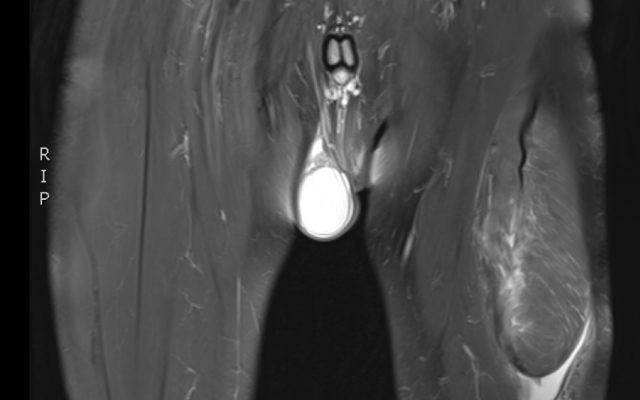

Een 49-jarige man met een blanco voorgeschiedenis bezocht de polikliniek Orthopedie vanwege een pijnlijke zwelling van zijn linker bovenbeen. De zwelling was 10 dagen geleden acuut ontstaan tijdens het zaalvoetballen, na een harde trap tegen de grond. Met name traplopen was pijnlijk. Ondanks frequent gebruik van ijskompressen, nam de zwelling niet af. Bij lichamelijk onderzoek zien wij aan de voorzijde van het bovenbeen een prominente zwelling die gevoelig is bij aanraking (figuur a). De zwelling had een glad aspect, was goed afgrensbaar en lag los van de huid, maar zat vast aan de onderlaag. De kracht van de M…